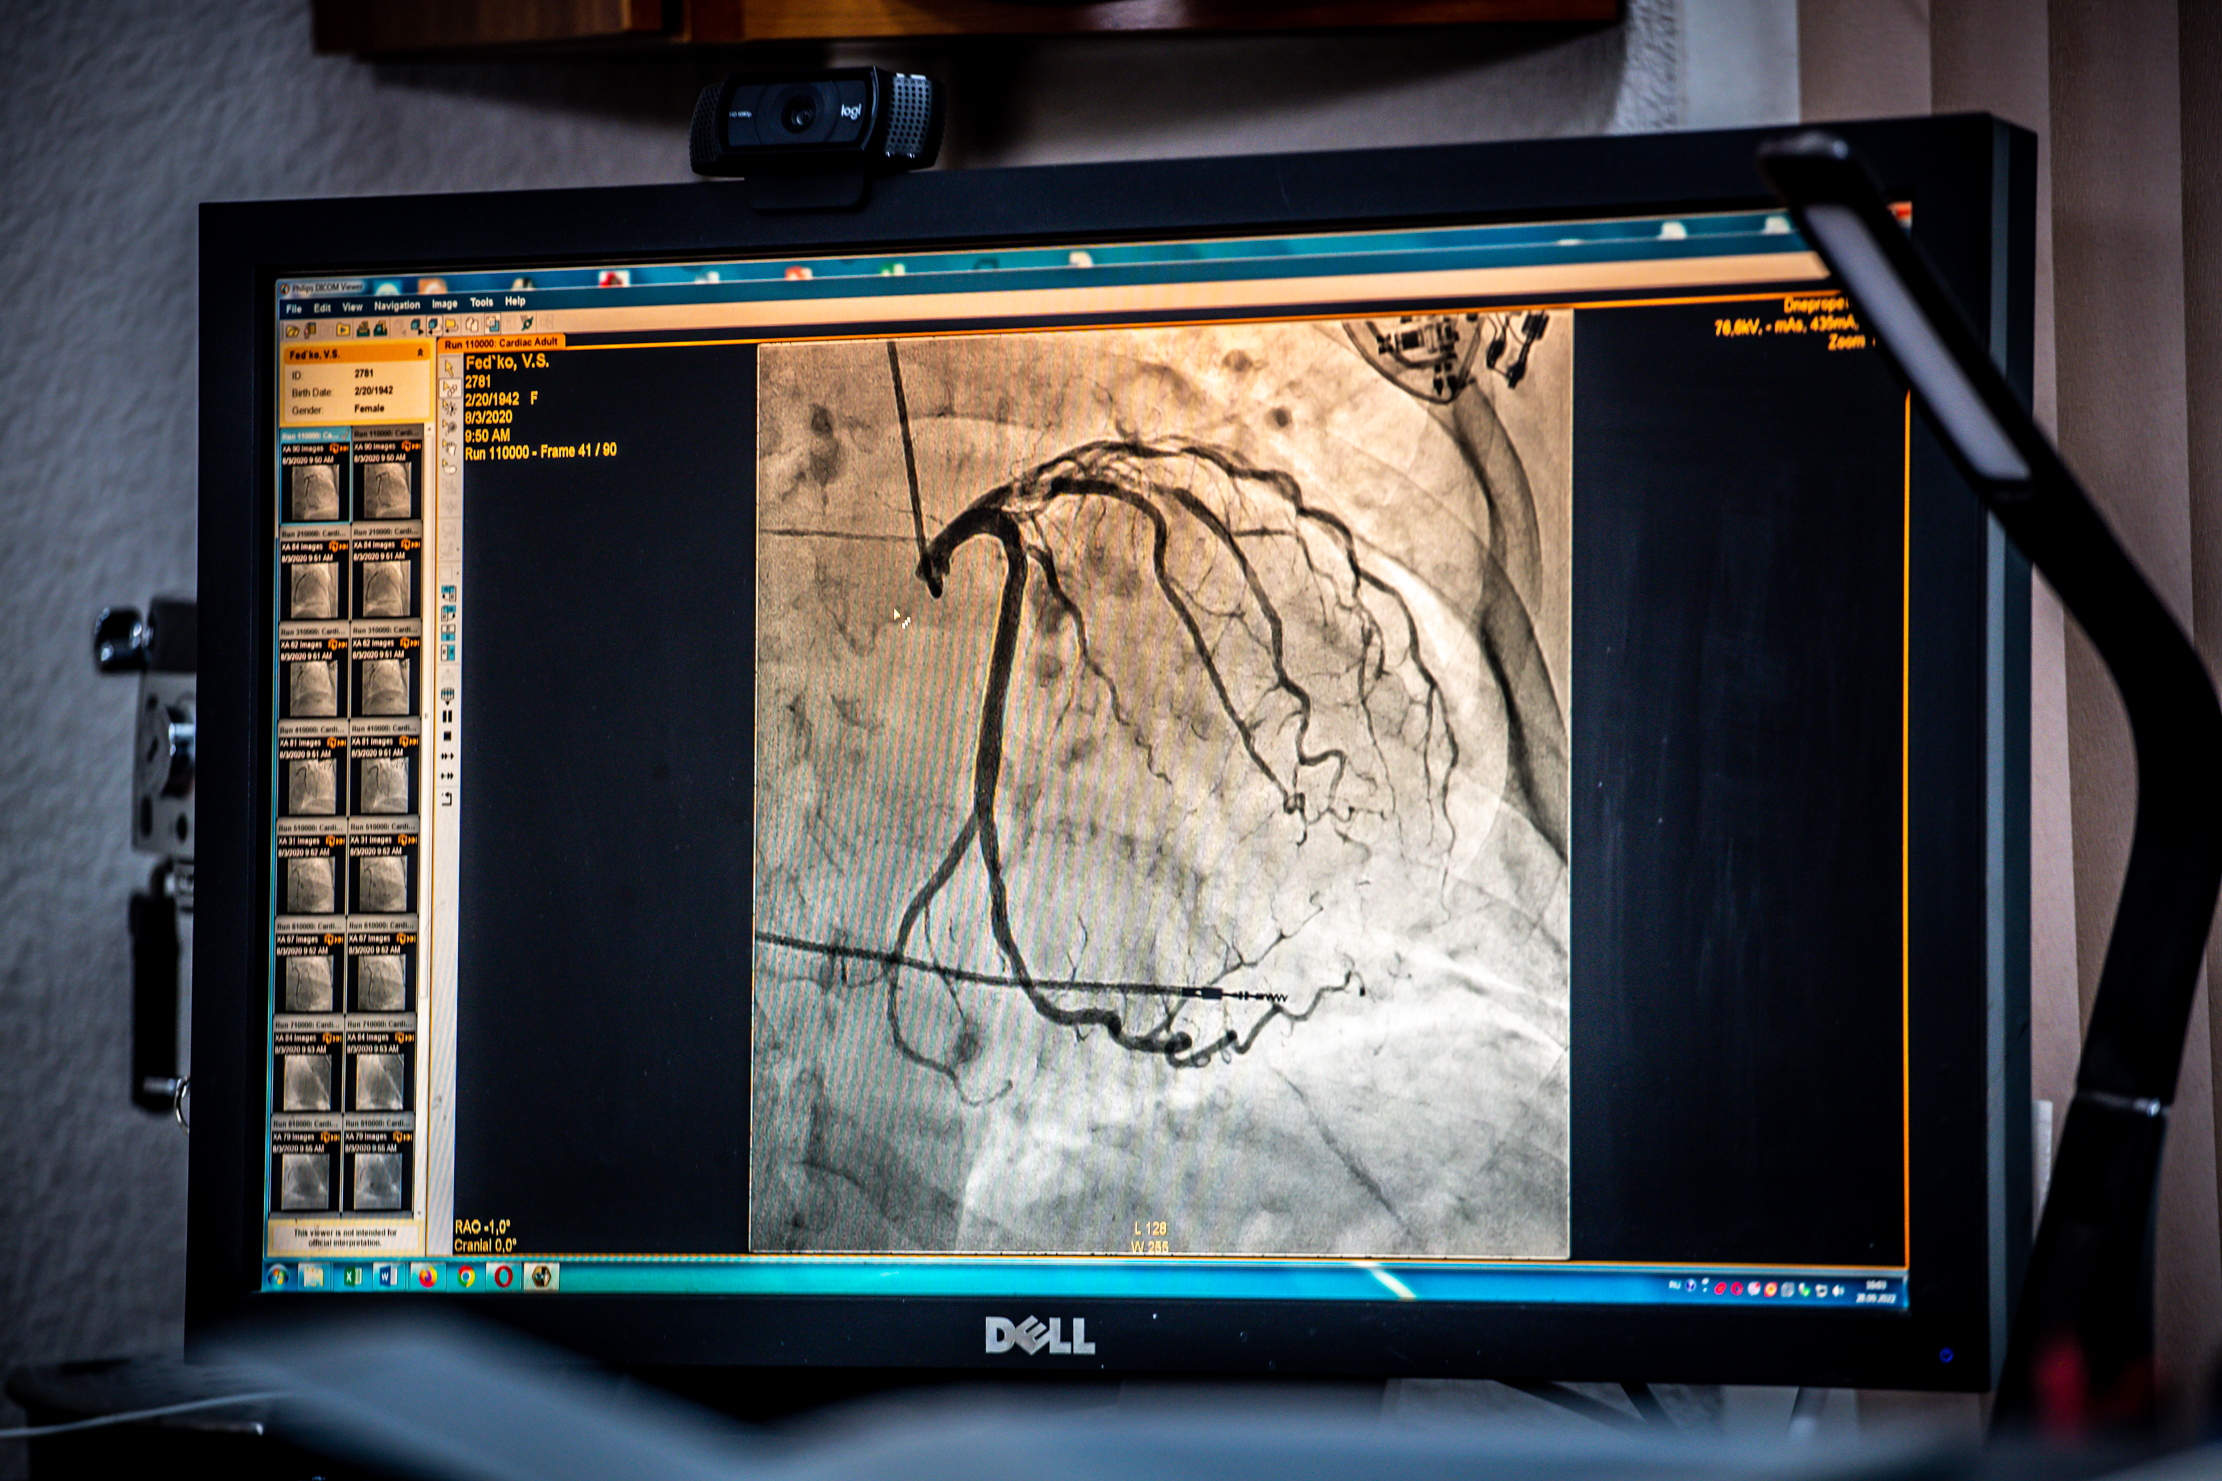

«У нас був 33-річний військовий з вогнепальним осколковим пораненням грудної клітини. Уламок пройшов через легеню, потім серце та застряг у життєво-небезпечній ділянці, – пригадує Сергій. – Інколи цей шматок ворожого металу складно знайти. На рентгені ти його бачиш. Заходиш у серце і не знаходиш, бо він прикритий тканинами».

Такі операції можуть тривати від двох до п’яти годин. Проводять їх на відкритому серці.

«Ми зупиняємо серце. Пацієнт не дихає і стає холодним. Поки оперуємо, працює апарат штучного кровообігу. По закінченню, зігріваємо людину, «включаємо» серце, дихання та повертаємо на світ Божий», – пояснює кардіохірург.